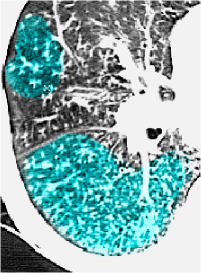

III. Candidate Pattern Selection: Our candidate detection method comes from a learning perspective such that we assign every internal voxel of the lung a membership value reflecting the size (i.e., scale) of the homogeneous region that the voxel belongs to. To do this, we use a locally adaptive scale based filtering method called ball-scale (or b-scale for short) [2]. b-scale is the simplest form of a locally adaptive scale where the scene is partitioned into several scale levels within which every voxel is assigned the size of the local structure it belongs. For instance, voxels within the large homogeneous objects have highest scale values, and the voxels nearby the boundary of objects have small scale values. Because of this fact and the fact in II.(a), we draw the conclusion that TIB patterns constitute only small b-scale values, hence, it is highly reasonable to consider voxels with small b-scale values as candidate TIB patterns. Moreover, it is indeed highly practical to discard voxels with high b-scale values from candidate selection procedure. Fig. 2 (candidate selection) and Fig. 3(b) show selected b-scale regions as candidate TIB patterns. A detailed description of the b-scale algorithm is presented in [2].

Based on the observation in training, TIB patterns most likely occur in the regions inside the lung with certain ranges (i.e, blue and yellow regions). This observation facilitates one practically useful fact in the algorithm that, in the feature extraction process, we only extract features if and only if at least “one” b-scale pattern exists in the local region as well as Willmore energy values of pixels lie in the interval observed from training. Moreover, considering the Willmore energy has a role as hard control on feature selection and computation, it is natural to investigate their ability to segment images. We present a segmentation framework in which every voxel is described by the proposed shape features. A multi-phase level set [6] is then applied to the resulting vectorial image and the results are shown in Fig. 3(g). First and second columns of the Fig. 3(g) show segmented structures and the output homogeneity maps showing segmented regions in different grey-level, respectively. Although segmentation of small airway structures and pathological patterns is not the particular aim of this study, the proposed shape features show promising results due to their discriminative power.